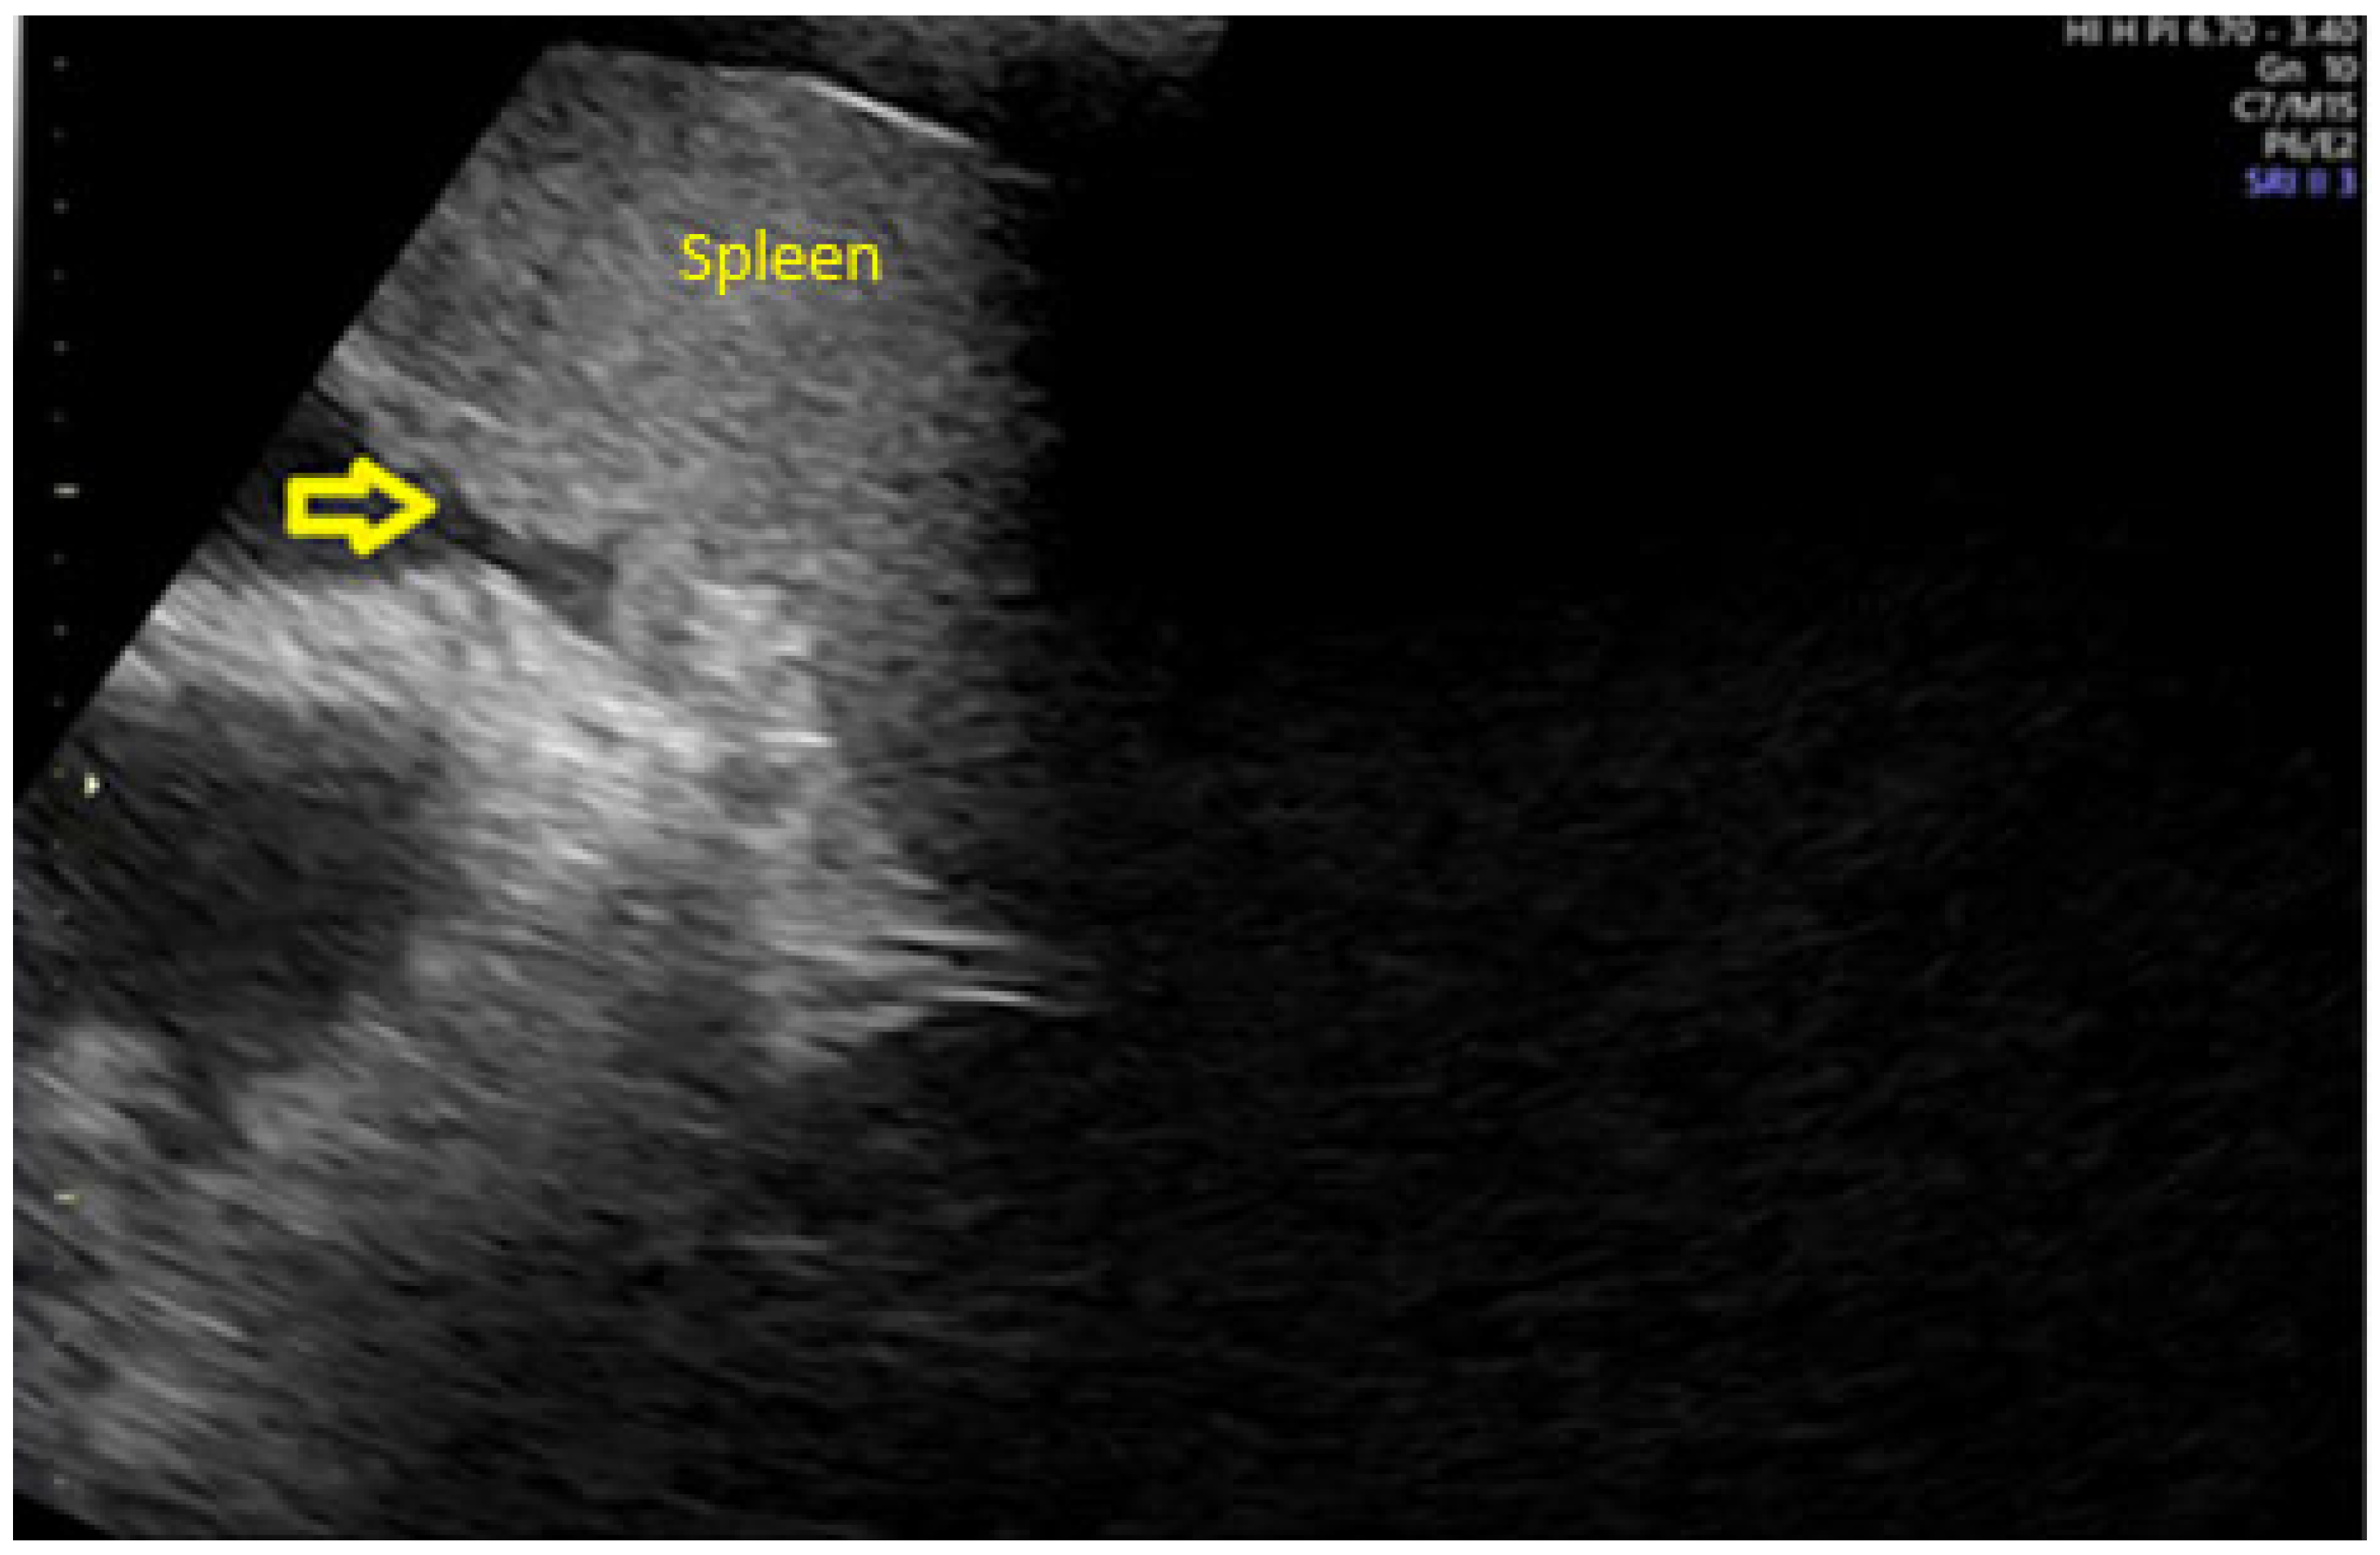

- Testa, A.C.; Ludovisi, M.; Mascilini, F.; Di Legge, A.; Malaggese, M.; Fagotti, A.; Fanfani, F.; Salerno, M.G.; Ercoli, A.; Scambia, G.; et al. Ultrasound evaluation of intra-abdominal sites of disease to predict likelihood of suboptimal cytoreduction in advanced ovarian cancer: A prospective study. Ultrasound Obstet. Gynecol. 2012, 39, 99–105. [Google Scholar] [CrossRef]

- Fischerova, D.; Zikan, M.; Semeradova, I.; Slama, J.; Kocian, R.; Dundr, P.; Nemejcova, K.; Burgetova, A.; Dusek, L.; Cibula, D. Ultrasound in preoperative assessment of pelvic and abdominal spread in patients with ovarian cancer: A prospective study. Ultrasound Obstet. Gynecol. 2017, 49, 263–274. [Google Scholar] [CrossRef]

- Tomasinska, A.; Stukan, M.; Badocha, M.; Myszewska, A. Accuracy of Pretreatment Ultrasonography Assessment of Intra-Abdominal Spread in Epithelial Ovarian Cancer: A Prospective Study. Diagnostics 2021, 11, 1600. [Google Scholar] [CrossRef]